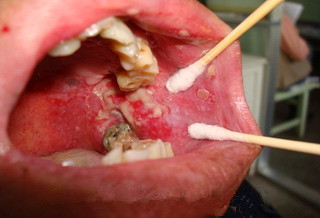

后来的一年里区某就开始找医院,找药吃,不少药吃了的确控制了病情,但是口舌生疮仍然时不时复发,心很累,最后是精疲力竭,吃药贴药都会复发。后来经朋友介绍找到广州市越秀区南粤医药研究所口腔黏膜专科,医院口腔粘膜科专家薛镇宇主任接诊了区某,区某来院时口腔左侧上下牙根中间的部位长了较大的的溃疡,且溃疡侵犯口腔黏膜较深层,伴淋巴肿大的(见:治疗前图片)。薛镇宇采用了“中西医四联疗法”为区某诊治。仅仅7天,区某的病情得到了明显的改善,治疗差不多一个月,口腔溃疡痊愈(见治疗后的图片)。现在过去大半年了,随访复查都没有复发过。

治疗前